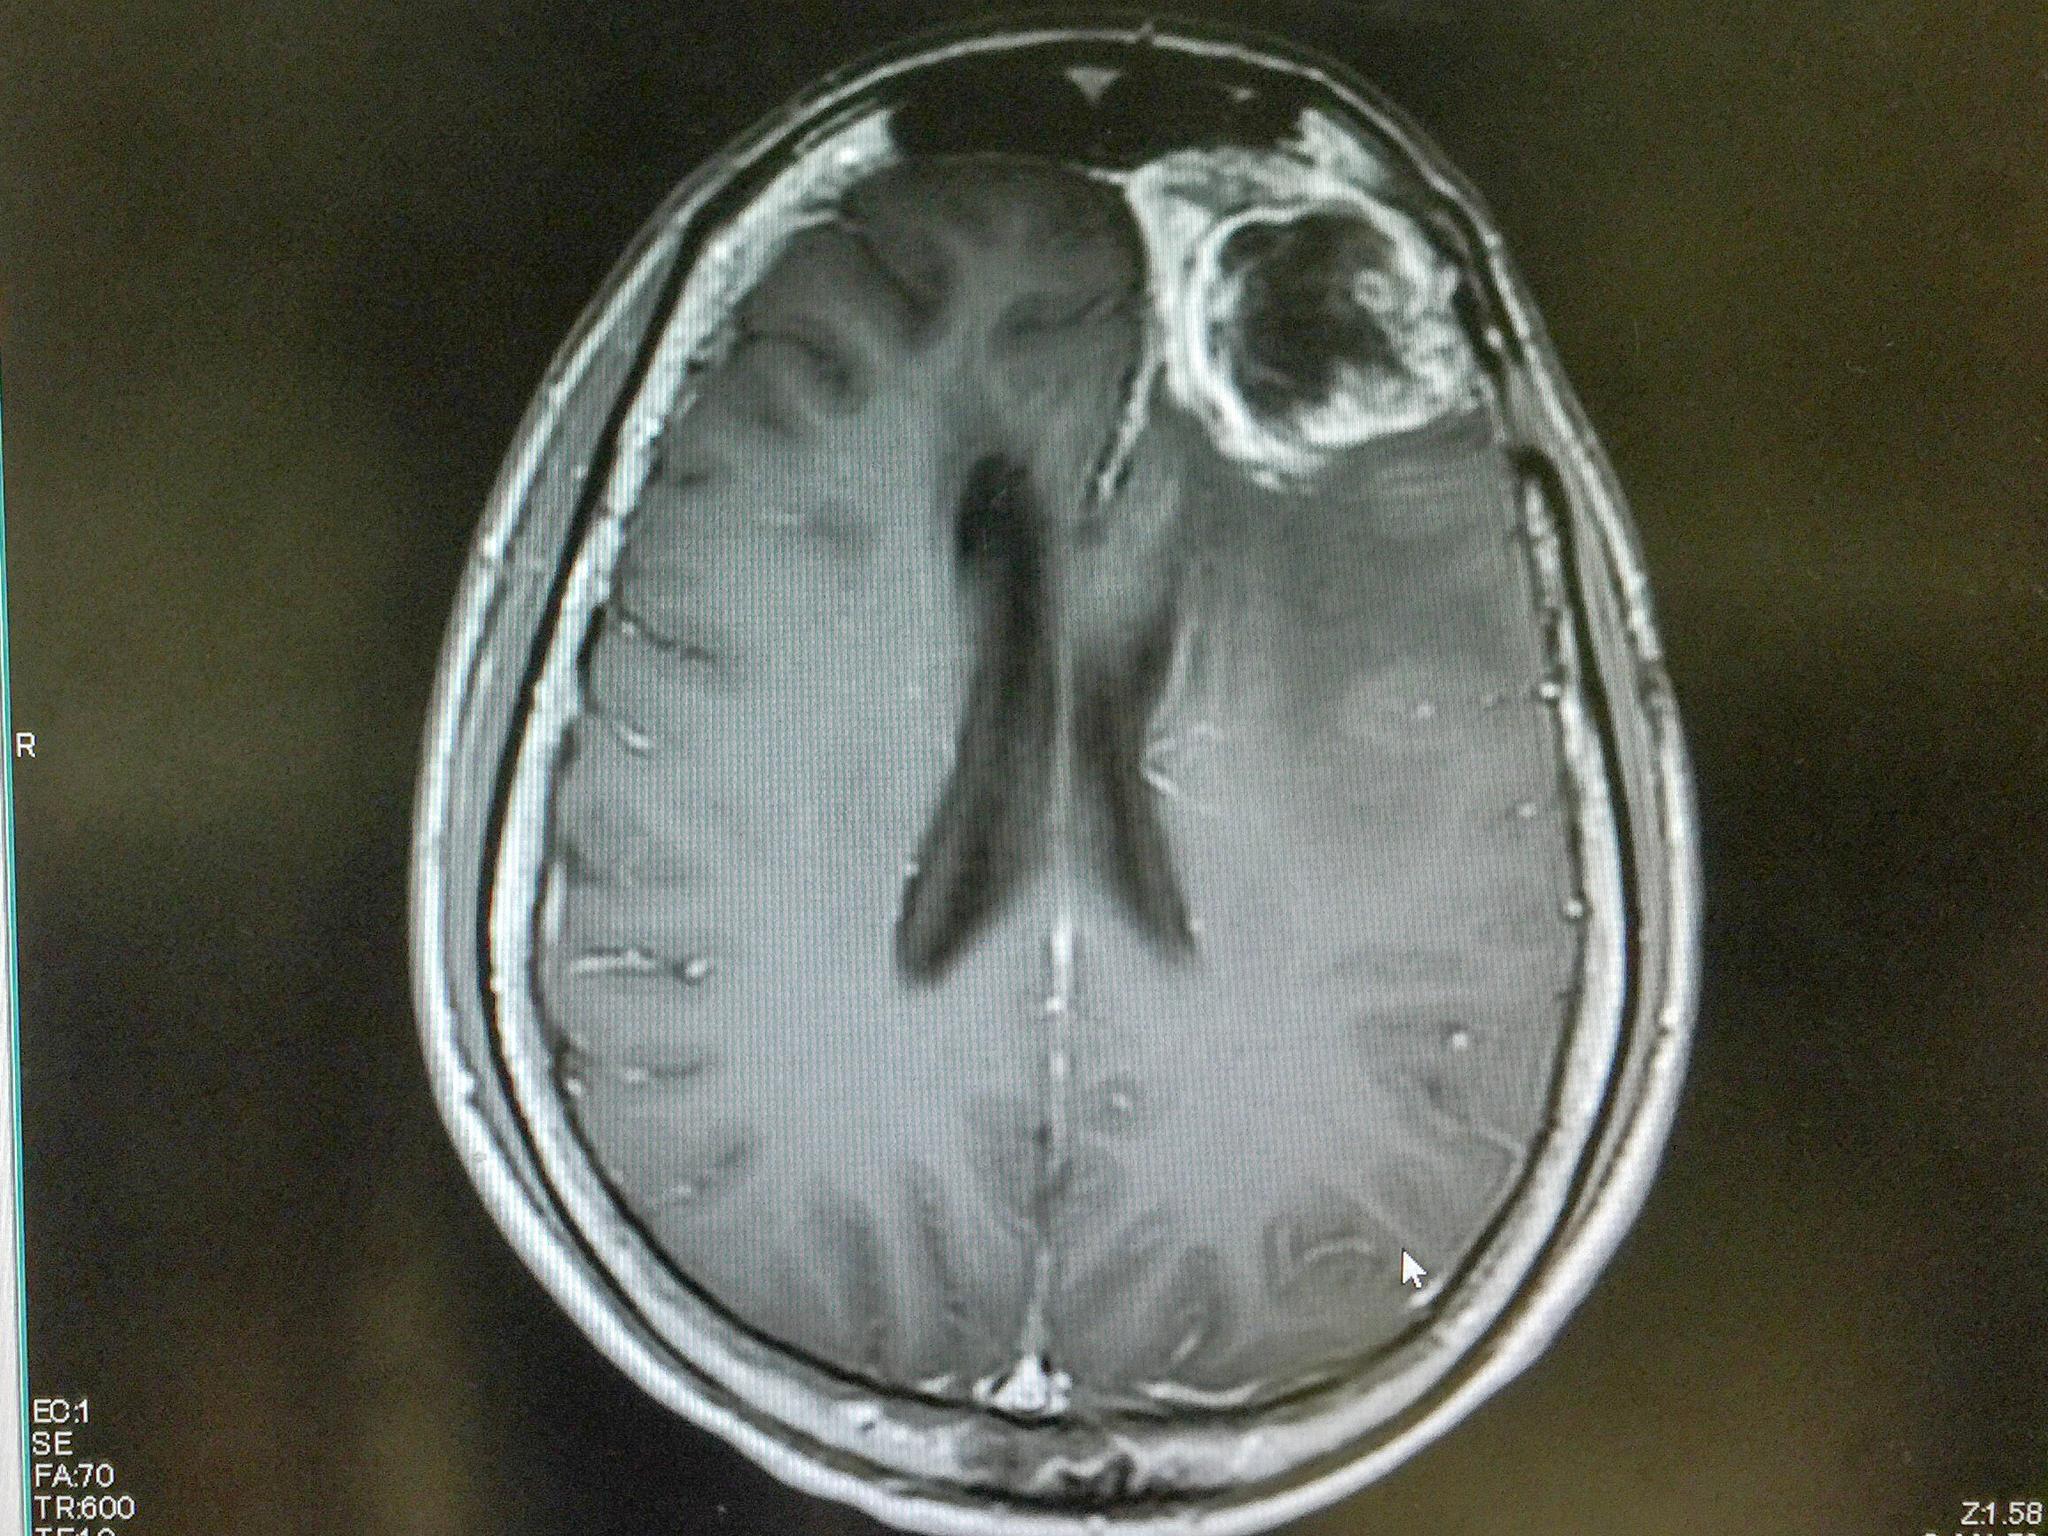

Микрофотографии гистологии глиобластомы головного мозга